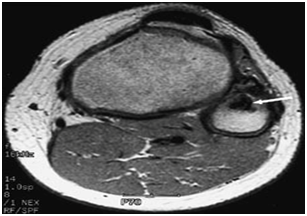

The classic plain radiographic findings of PVNS consist of cystic erosions, increased density of the synovium, secondary to hemosiderin deposition and peri-articular soft-tissue swelling with no calcification.8 Magnetic resonance imaging usually demonstrates key diagnostic features, which include joint effusion, elevation of the joint capsule, hyperplastic synovium and low signal intensity resulting from hemosiderin deposition.2 In patients with diffuse pigmented villonodular synovitis of the knee, magnetic resonance imaging (MRI) may show a large effusion, low signal intensity on both T1 and T2 weighted images (because of hemosiderin deposition), hyperplastic synovium and occasional bony erosions (Figure 1) and (Figure 2).

Figure 2 T2-weighted MRI scan showing a lesion in the proximal fibula (arrow) that has a low intensity consistent with pigmented villonodular synovitis.